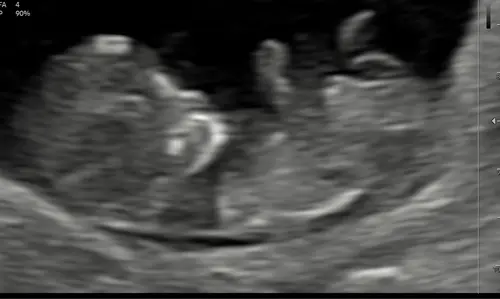

Hier 9 weken en 1 dag 🥰 mooi kloppend hartje en armen en benen druk aan het bewegen